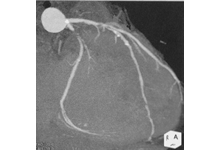

図4. 冠動脈CT検査

造影剤を注射し、撮影して得られた画像

から冠動脈の状態が分かります。 - 4.狭心症の治療は?